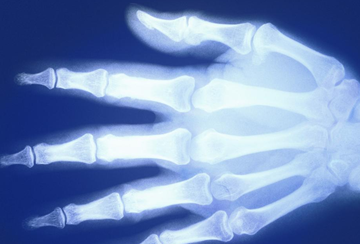

You may have heard of a bone mineral density (BMD) test. This is also known as a “DEXA” or “DXA” test (Dual Energy R-Ray Absorptiometry). This is a safe, painless way to measure the density of your bones. During the test, you lay fully clothed on a table while small amounts of x-rays are transmitted through your bones. The amount of x-rays passing through your bones is measured. The greater the amount of x-rays that pass through, the less dense your bones are. The density of bones is called bone mineral density (BMD).